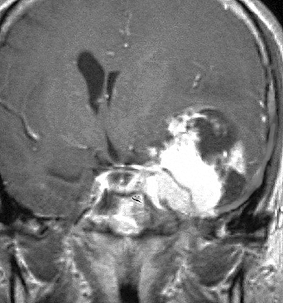

左は,造影剤を使ったガドリニウム増強MRIです。腫瘍が白く丸く見えます。右はフレア画像で,腫瘍の周囲の脳浮腫(脳のはれ)です。左前頭葉が,かなり強くはれています。この腫瘍は小さいのですが,脳のはれが強すぎるので手術摘出したほうがいいです。浮腫が悪化すると,てんかん発作や認知機能低下がでる可能性があります。